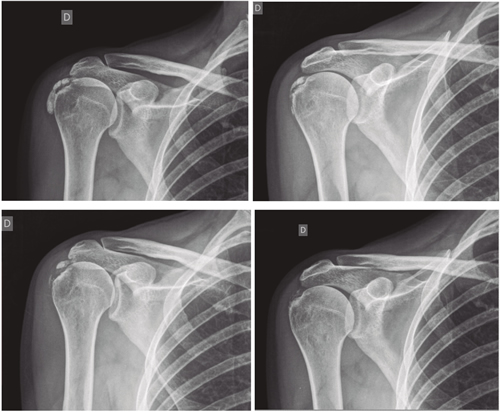

Figura 1